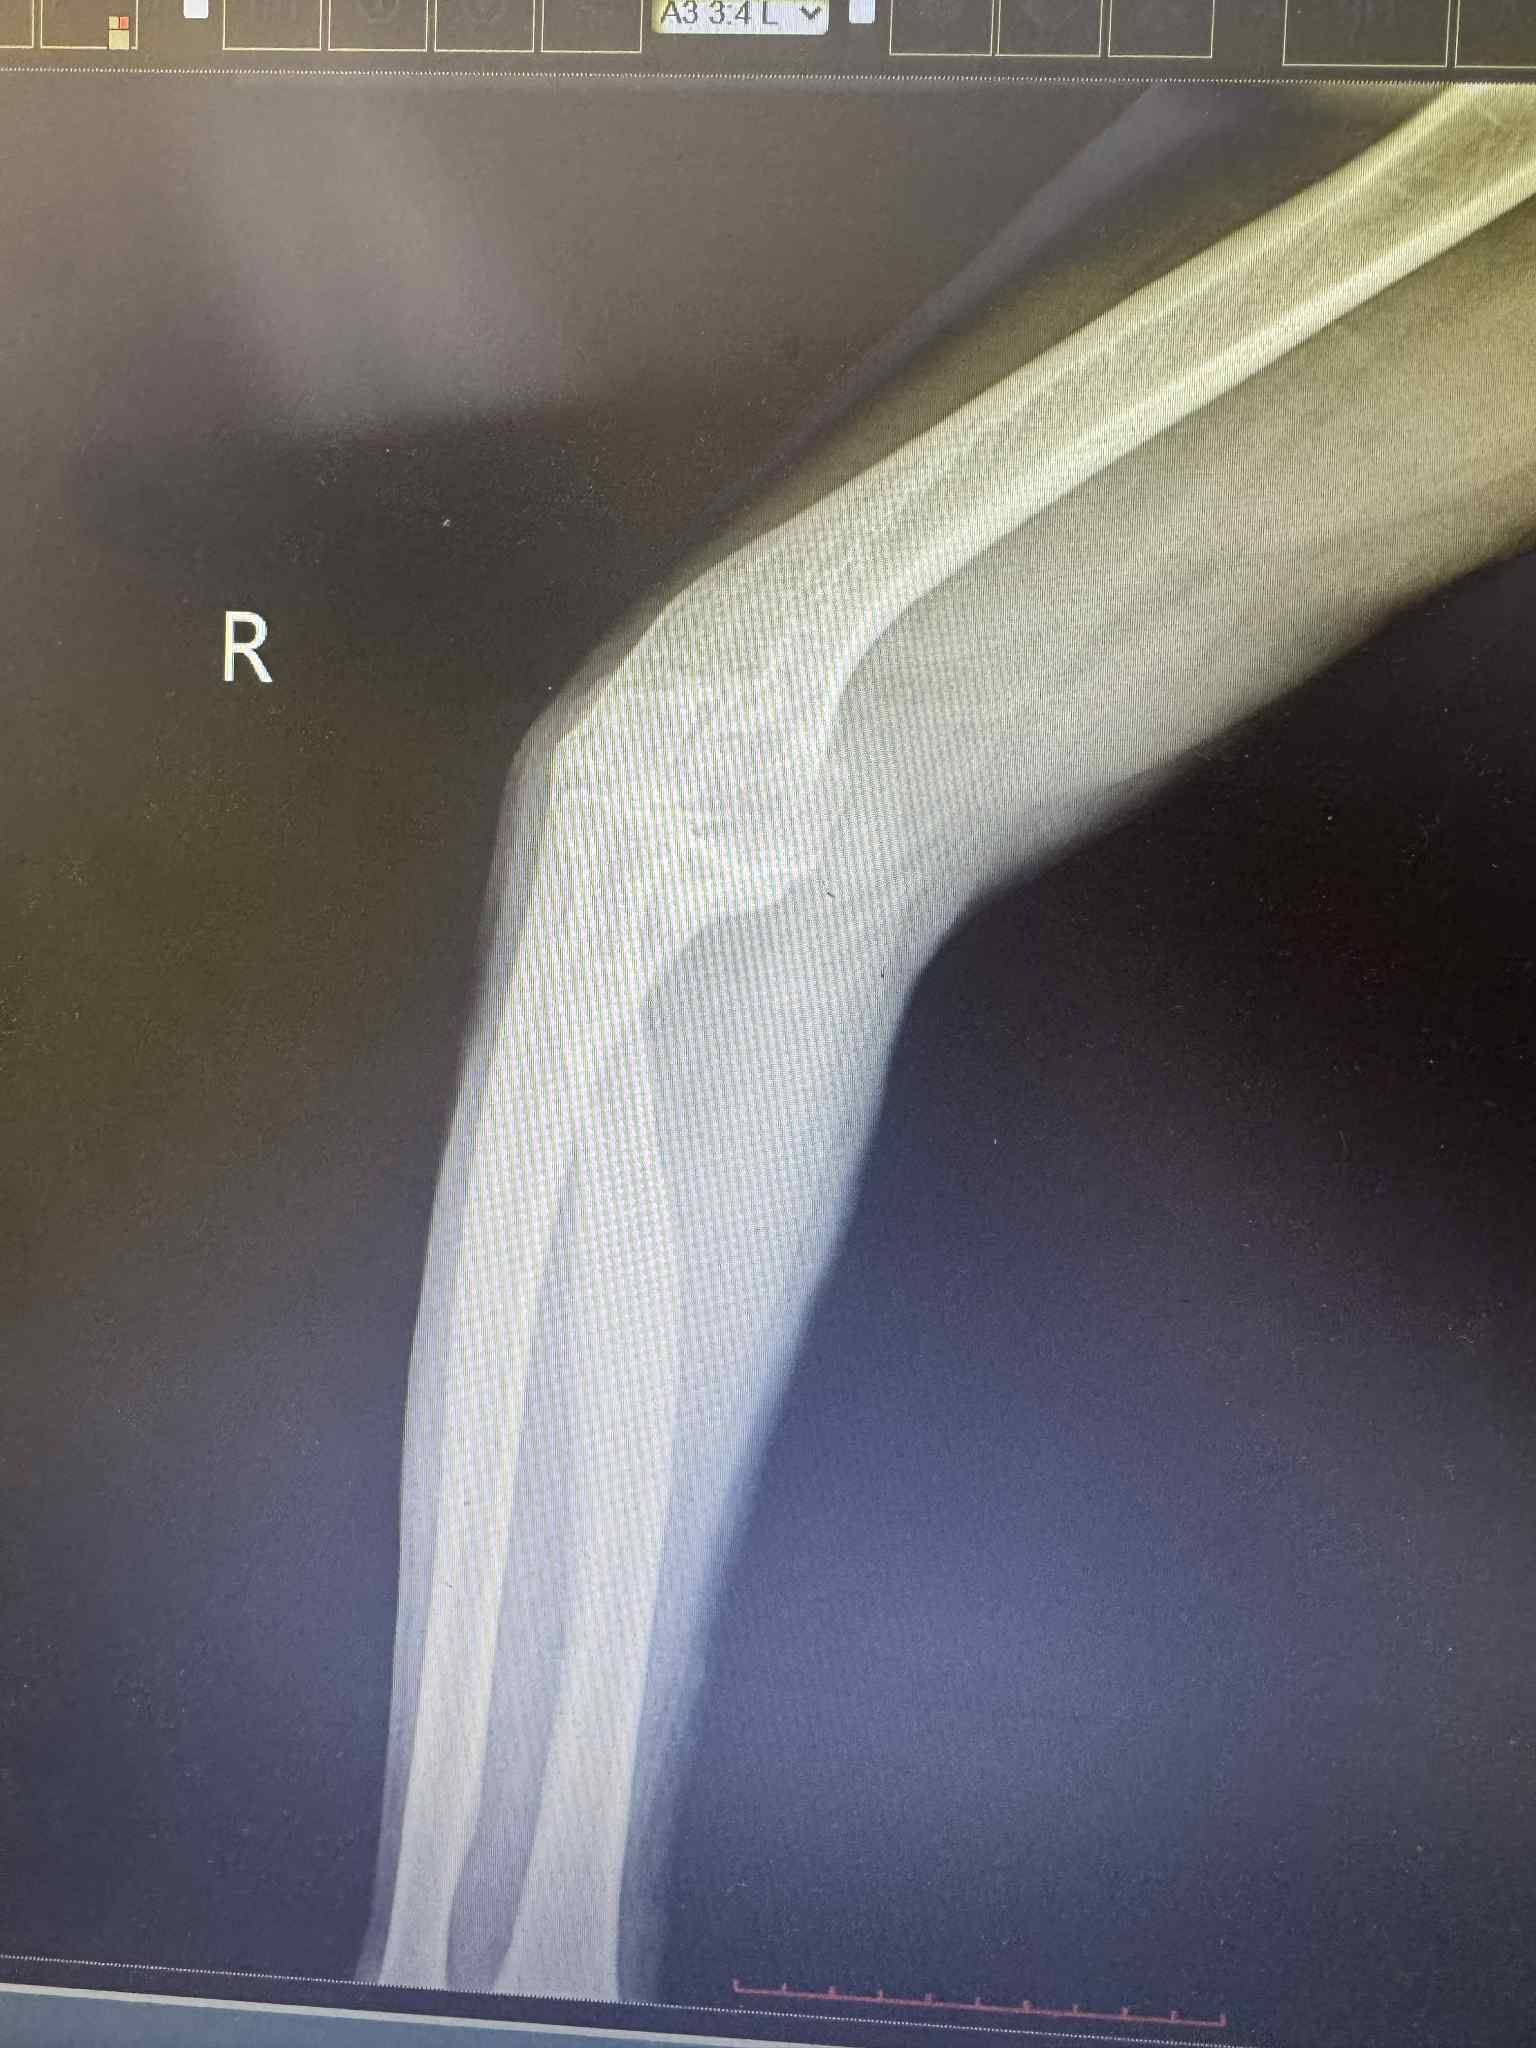

Төв аймгийн Нэгдсэн эмнэлгийн мэс заслын тасгийн гэмтлийн эмч нар Гэмтэл согог судлалын үндэсний төвийн эмч нартай хамтран орон нутагтаа анх удаа тохойн үе бүтэн солих мэс заслыг амжилттай нэвтрүүллээ.